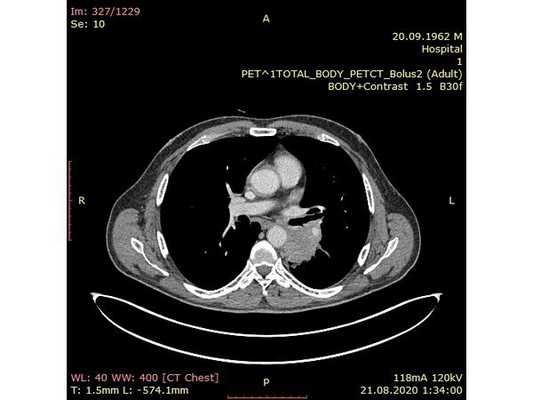

31.07.2020 мужчина 57 лет обратился в Клиническую больницу № 2 АО ГК МЕДСИ с данными компьютерной томографии, где выявлено центральное новообразование в корне нижней доли левого лёгкого.

Чтобы провести первичное стадирование опухоли, пациенту проведена позитронно-эмиссионная томография в сочетании с компьютерной томографией (ПЭТ-КТ). По данным исследования, выявлена метаболически активная опухоль в корне левого лёгкого с бугристыми контурами размерами 41 х 43 мм. В толще опухоли проходят нижнедолевой бронх и бронх 6-го сегмента левого лёгкого, просветы бронхов значительно сужены. Нижняя доля левого лёгкого уменьшена в размерах за счёт того, что сегменты 6, 9 и 10 субтотально (частично) инфильтрированы и безвоздушны. Лимфатические узлы корня лёгкого и средостения не увеличены в размерах и не накапливают радиофармпрепарат (РФП), который был введён пациенту перед обследованием внутривенно. Других очаговых образований и очагов гиперметаболизма в организме не обнаружено.

При этом отмечено, что опухоль распространяется в средостение по нижней стенке левого главного бронха и широко прилежит к нижнегрудному отделу аорты (по заключению специалиста ПЭТ-КТ — имеется инвазия опухоли в ткани средостения и возможное врастание в стенку аорты). При самостоятельном пересмотре изображений отмечено, что "опухолевая" ткань, которая распространяется по нижней стенке левого главного бронха в средостение, не накапливает РФП (т. е. не является злокачественной), а стенка аорты в области "инвазии" опухоли имеет ровный чёткий контур и адвентициальную границу, что также свидетельствует об отсутствии онкологического процесса в этой области.